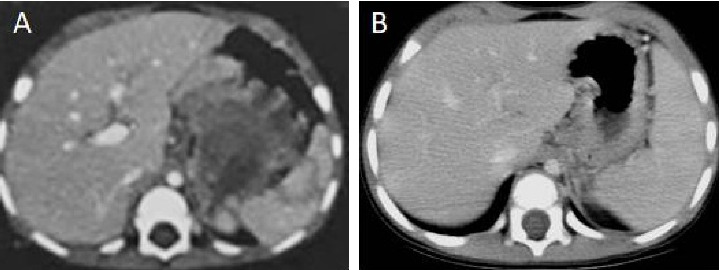

Up to one-third of germ cell tumors are extragonadal neoplasms, with yolk sac tumors (YSTs) being the most common malignant histology. This report describes the successful multimodal management of a primary YST of the stomach in a 2-year-old boy. The child presented with melena, and further evaluation revealed a mass lesion in the cardia of the stomach. A biopsy established a diagnosis of a YST, which correlated with an elevated serum alpha-fetoprotein level. The child received three cycles of chemotherapy consisting of cisplatin, etoposide, and bleomycin (PEB), followed by surgical resection in the form of proximal gastrectomy. After an uneventful recovery from surgery, he received an additional three cycles of PEB and has remained disease-free for 7 years. This case highlights the potential for the occurrence of a relatively rare childhood tumor at an unusual site, which can pose diagnostic challenges. However, careful evaluation and meticulous management can lead to favorable outcomes.